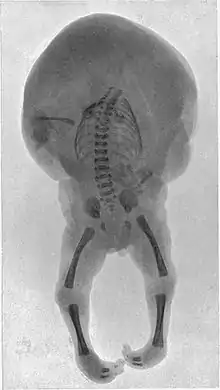

Acardiac twin

The acardiac twin is a parasitic twin that fails to properly develop a heart, and therefore generally does not develop the upper structures of the body. The parasitic twin, little more than a torso with or without legs, receives its blood supply from the host twin by means of an umbilical cord-like structure (which often only has 2 blood vessels, instead of 3), much like a fetus in fetu, except the acardiac twin is outside the host twin's body. Although the reason is not fully understood, it is apparent that deoxygenated blood from the pump twin is perfused to the acardiac twin. The acardiac twin grows along with the pump twin, but due to inadequate oxygenation it is unable to develop the structures necessary for life, and presents with dramatic deformities.

Although no two acardiac twins are alike, twins with this disorder are grouped into 4 classes: Acephalus, anceps, acormus, and amorphus.

- Acephalus – The most common type, lacking a head, though it may have arms. Thoracic organs are generally absent, and disorganized & unidentifiable tissues take their place.

- Anceps – The acardius has most body parts, including a head with face and incomplete brain. Organs, though present, are crudely formed.

- Acormus – This type has no body, only a head without a neck; the umbilical cord is attached to the head.

- Amorphus – This extreme form not only lacks a head and limbs, but may or may not lack any internal organs, and consists of tissue with vessels branching from the umbilical cord. Some may only be stem cell tumors.